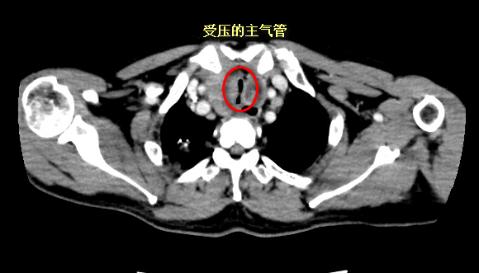

冯起校主任分析了唐叔的胸部CT后,指出呼吸困难是由于食管中上段恶性肿瘤侵犯周围淋巴结,导致主支气管受压狭窄。由于食管肿瘤病变非常广泛,唐叔很快出现了喘憋、端坐呼吸的症状,行气管插管仍不能完全缓解,急送内镜中心行支气管镜检查,发现气管中上段狭窄竟达到了80%。

治疗迫在眉睫,冯起校在20分钟内就成功在主支气管置入18*60mm的金属裸支架,当支架释放后,唐叔胸闷、呼吸困难的症状立刻得到了缓解,病情逐步趋于稳定。气管支架的置入为唐叔后续的抗肿瘤治疗赢得了宝贵的时间。